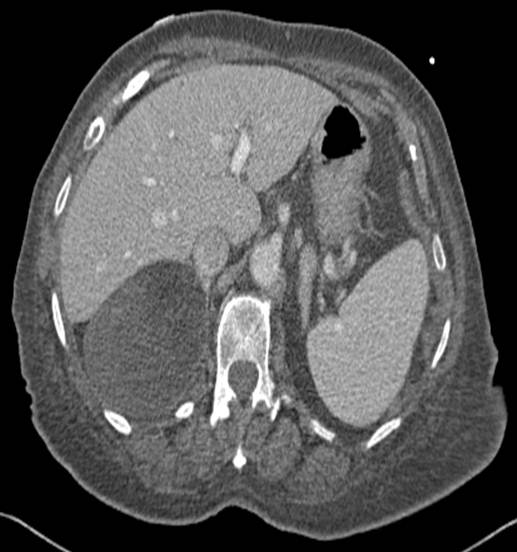

Non-enhanced CT scans for suspected renal colic often detect incidental findings.

Pelvic CT with filtered back projection and 50% ASIR reduces dose.

Filtered back projection and ASIR50 reduces dose in pelvic CT.